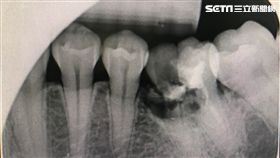

狂嗑零食恐牙崩!飯後馬上刷牙錯錯錯

年節將至,跟親友相聚時,免不了吃吃喝喝、嗑嗑零食,但...

過年宅在家?牛軋糖、瓜子恐吃到牙裂

農曆春節將至!不少民眾會在過年年假期間大吃大喝,但還...